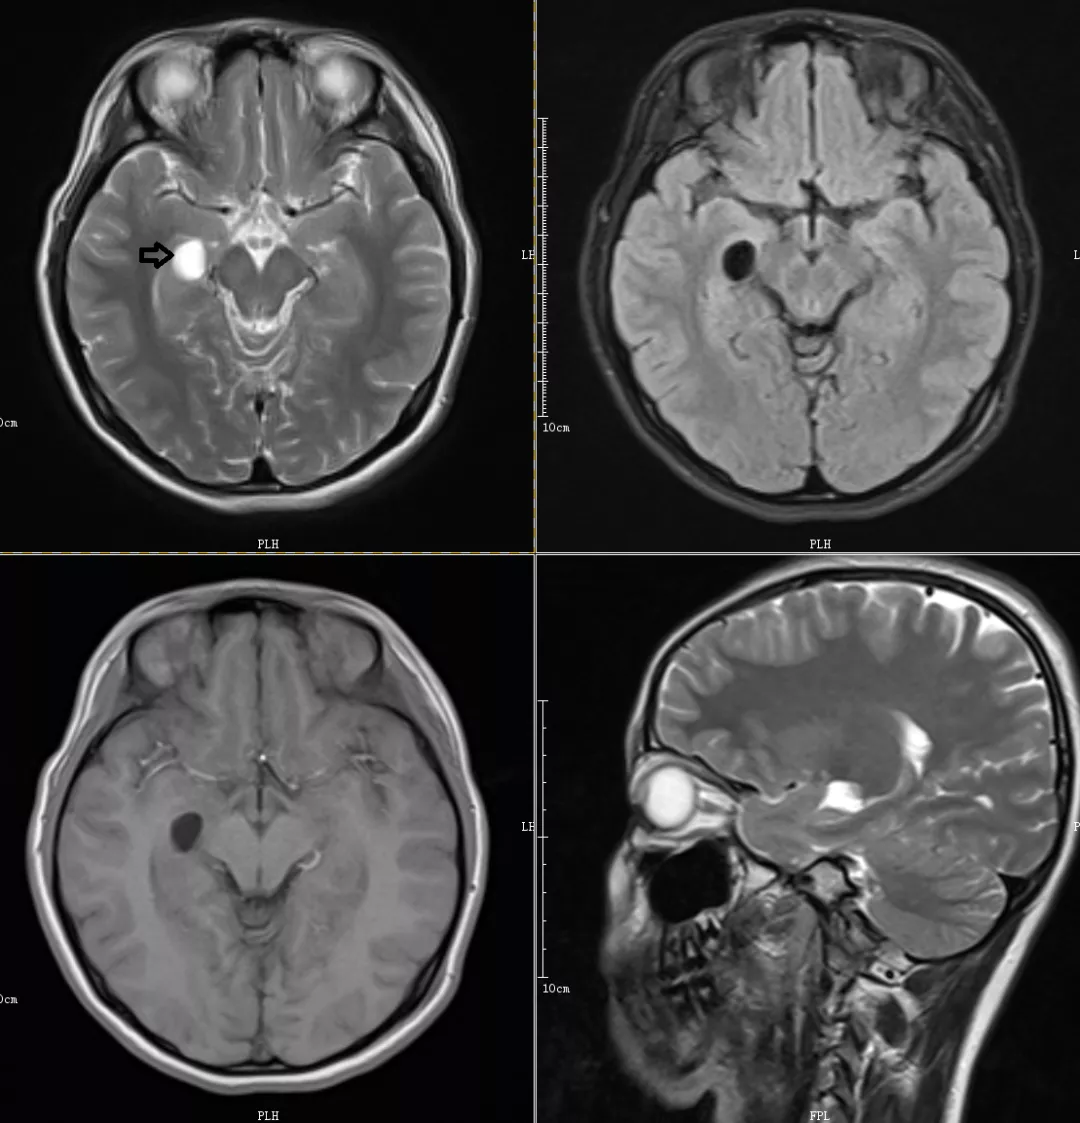

CASE1

右侧脉络膜裂囊肿

MRI表现:显示脉络膜裂处典型的囊肿性病变,病灶为圆形、卵圆形,T2WI为高信号,T1WI、FLAIR及DWI均为低信号,与脑脊液信号相同;病灶周围脑实质无异常信号,边缘光滑锐利。增强扫描无强化。冠状位可清楚的显示囊肿位于脉络膜裂内,其外下方可见侧脑室颞角呈点状或条状结构,矢状位显示颞叶内侧卵圆形或梭形囊肿,其长轴沿后上至前下斜行。

脉络膜裂囊肿属于神经上皮囊肿,可能因胎儿发育时期在沿脉络膜裂形成原始脉络膜丛的过程中发生障碍而形成,多见于颞叶内下部脉络膜裂处。体积较小者无临床意义。

双侧Meckel对称

CASE2

双侧Meckel不对称